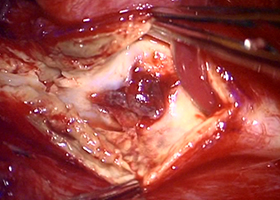

てんかんの治療は抗てんかん薬などの薬での治療が中心ですが、薬物治療で発作の抑制が困難な難治性てんかんに対しては、様々の検査を行い、てんかん焦点を同定して外科的に切除する治療があります。この治療により、抗てんかん薬の減量が可能になることや、てんかんの回数を減らす効果が期待されます。また、てんかん焦点の特定が困難な場合や、てんかん焦点が脳の運動や言語など、重要な機能に関連する領域にある場合は、手術により、脳表に電極を留置し、脳表から直接脳波を記録したり、電気刺激したりすることによって、てんかん焦点を同定しつつ、切除できるかどうかを検討することがあります。切除が困難な症例でも、迷走神経刺激療法という手術で治療可能な場合があります。この治療は、首の左側にある迷走神経に電極を巻き付け、電気刺激を行うことによって、てんかん発作の頻度や程度を軽くする治療です。

-

後頭葉てんかんの手術例です。 -

左:開頭して、脳の表面に電極を置きます。

中:脳表の電極から脳波を記録し、

てんかん焦点を同定します。

右:てんかん焦点を切除することで、

発作のコントロールが可能です。